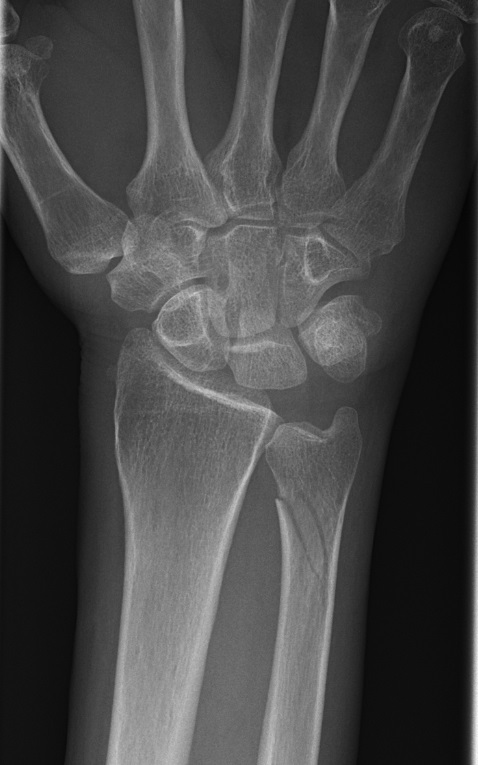

Distal enkel, minimalt felställd, stabil fraktur

Dorsal gipsskena 4-6 veckor med återbesök med röntgenkontroll efter 1 och ev. även 2 veckor. [6]

Distal stabil ulnafraktur, behandlades med kort gipsskena 4 v